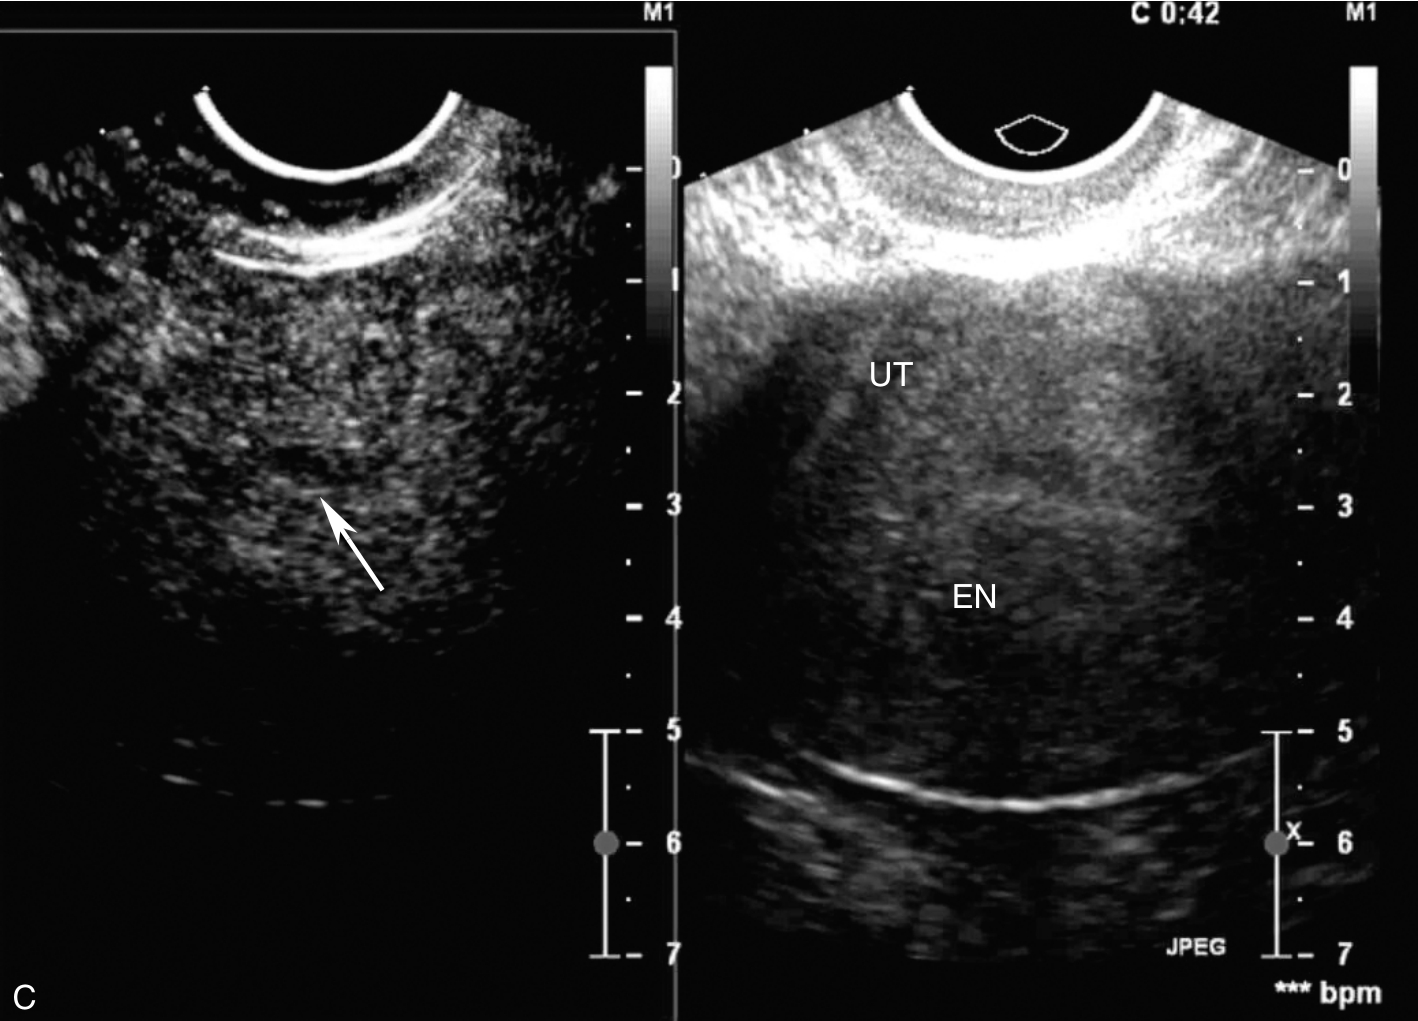

经阴道超声检查见图3-12-2。子宫前位,宫体大小为4.6cm×6.5cm×5.6cm,内膜居中,厚0.2cm(单层),肌壁回声欠均匀,未探及明显异常血流。宫颈查见囊性占位,最大径约3.1cm,液体欠清亮,周边未探及血流信号。右卵巢上查见囊性占位,大小为3.0cm×1.6cm×2.5cm,囊液欠清亮,囊壁可探及血流信号。左附件区未见占位。超声检查结果:右卵巢上囊性占位(多系良性),子宫颈腺囊肿。

图3-12-2 常规超声声像图

A.前位子宫的矢状切面;B.子宫横切面;C.右附件区囊性占位;D.宫颈囊性占位。UT:子宫;C:囊肿;Cx:宫颈。